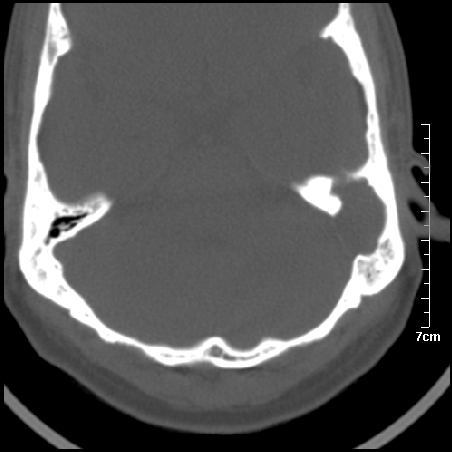

病例1

m/46y 头晕.耳鸣半月余 有乳突炎病史

左侧板障型乳突。